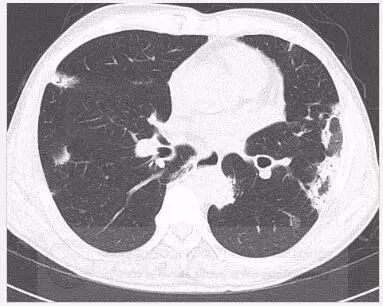

患者无特异性症状双肺斑片状实变的原因是丨以影识病